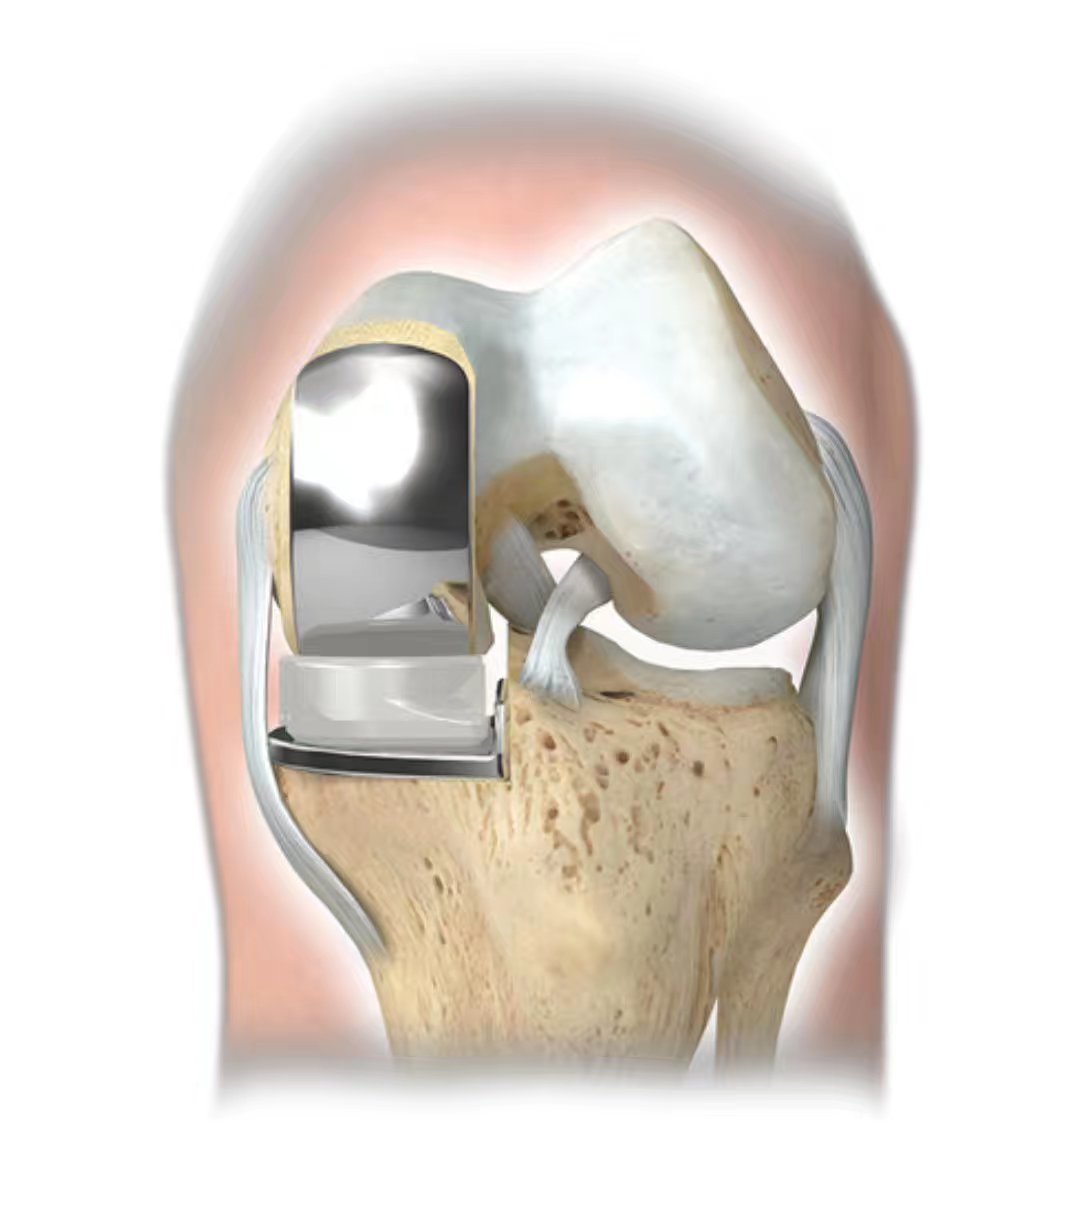

什么是膝关节单髁置换手术?

单髁置换术的手术要点及技巧